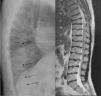

ML III occurs approximately between 3 and 5 years of age, with skeletal and facial abnormalities, short stature, normal intelligence or mild mental retardation, corneal opacity and scoliosis, unlike other forms of ML that have visceral involvement and a gloomy vital prognosis in childhood.2,3 In ML III, evolution is slow, and patients can reach up to the fifth decade of life.4 Bone alterations in children may be confused with juvenile idiopathic arthritis or scleroderma, primarily by involvement of the hands.5,6 The characteristic radiologic findings of the hands are small and irregular carpal bones and relatively wide proximal phalanges5 (Fig. 1). In the lumbar spine, vertebral dysplasia with irregular delineation of the vertebral bodies3 is confirmed on MRI (Fig. 2). In the pelvis, progressive hip dysplasia, with a flattened acetabulum and femoral head destruction with secondary coxarthrosis is seen2 (Fig. 3).